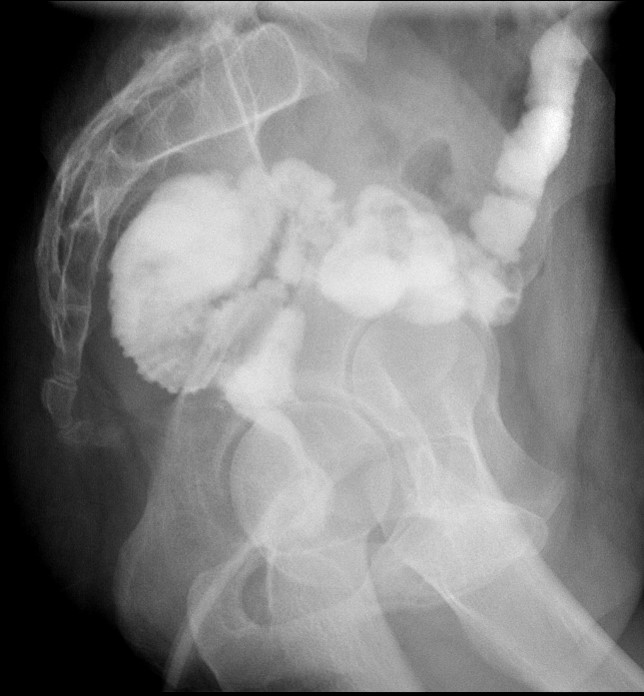

- The technologist will obtain a scout radiograph to include the upper abdomen. Evaluate for the location of the surgical chain sutures

(key image 1).

- There are usually two "sets" of surgical chain sutures.

- The first is located in the epigastric area at the level of the gastrojejunal anastomosis.

- The second is usually located in the left midabdomen. This is the site of the jejunojejunal anastomosis.

- If using water soluble contrast material or thin barium, start with the patient in the semi-recumbent position with the table tilted 30-45 degrees. If using bubbly barium, start in the upright position.

- Position the patient in the right posterior oblique position and have the patient take a sip of contrast material.

- Obtain a spot film of the contrast material filling the gastric pouch and proximal roux limb

(key image 2).

- Repeat steps b and c except have the patient positioned in the left posterior oblique position

(key image 3).

- If necessary, repeat with the patient in the supine position

- The technologist will take a post procedure radiograph to evaluate the upper abdomen

(key image 4).

- If the contrast material has not progressed beyond the jejunojejunal anastomosis on the first radiograph, have the technologist obtain a delayed radiograph (more than one may be needed). Once the contrast has progressed past the jejunojejunal anastomosis, the procedure is complete

(key image 5)

(key image 6)

(key image 7).

- It is preferable that patients are strict NPO for the 6 hours before the exam. This includes oral medications and water.

- Patients should only be given bubbly barium if they are currently drinking carbonated beverages.

- If there is a concern for a leak or if there is the possibility for urgent intervention (surgery, scope, etc.) use water soluble contrast material.

- Image the patient in the semi-upright supine, LPO, and RPO projections.

- If the patient has complaints of dysphagia, be sure to evaluate the esophagus.

- A full upper GI on a patient with this surgery will include images of the contrast as it passes beyond the jejunojejunal anastomosis.